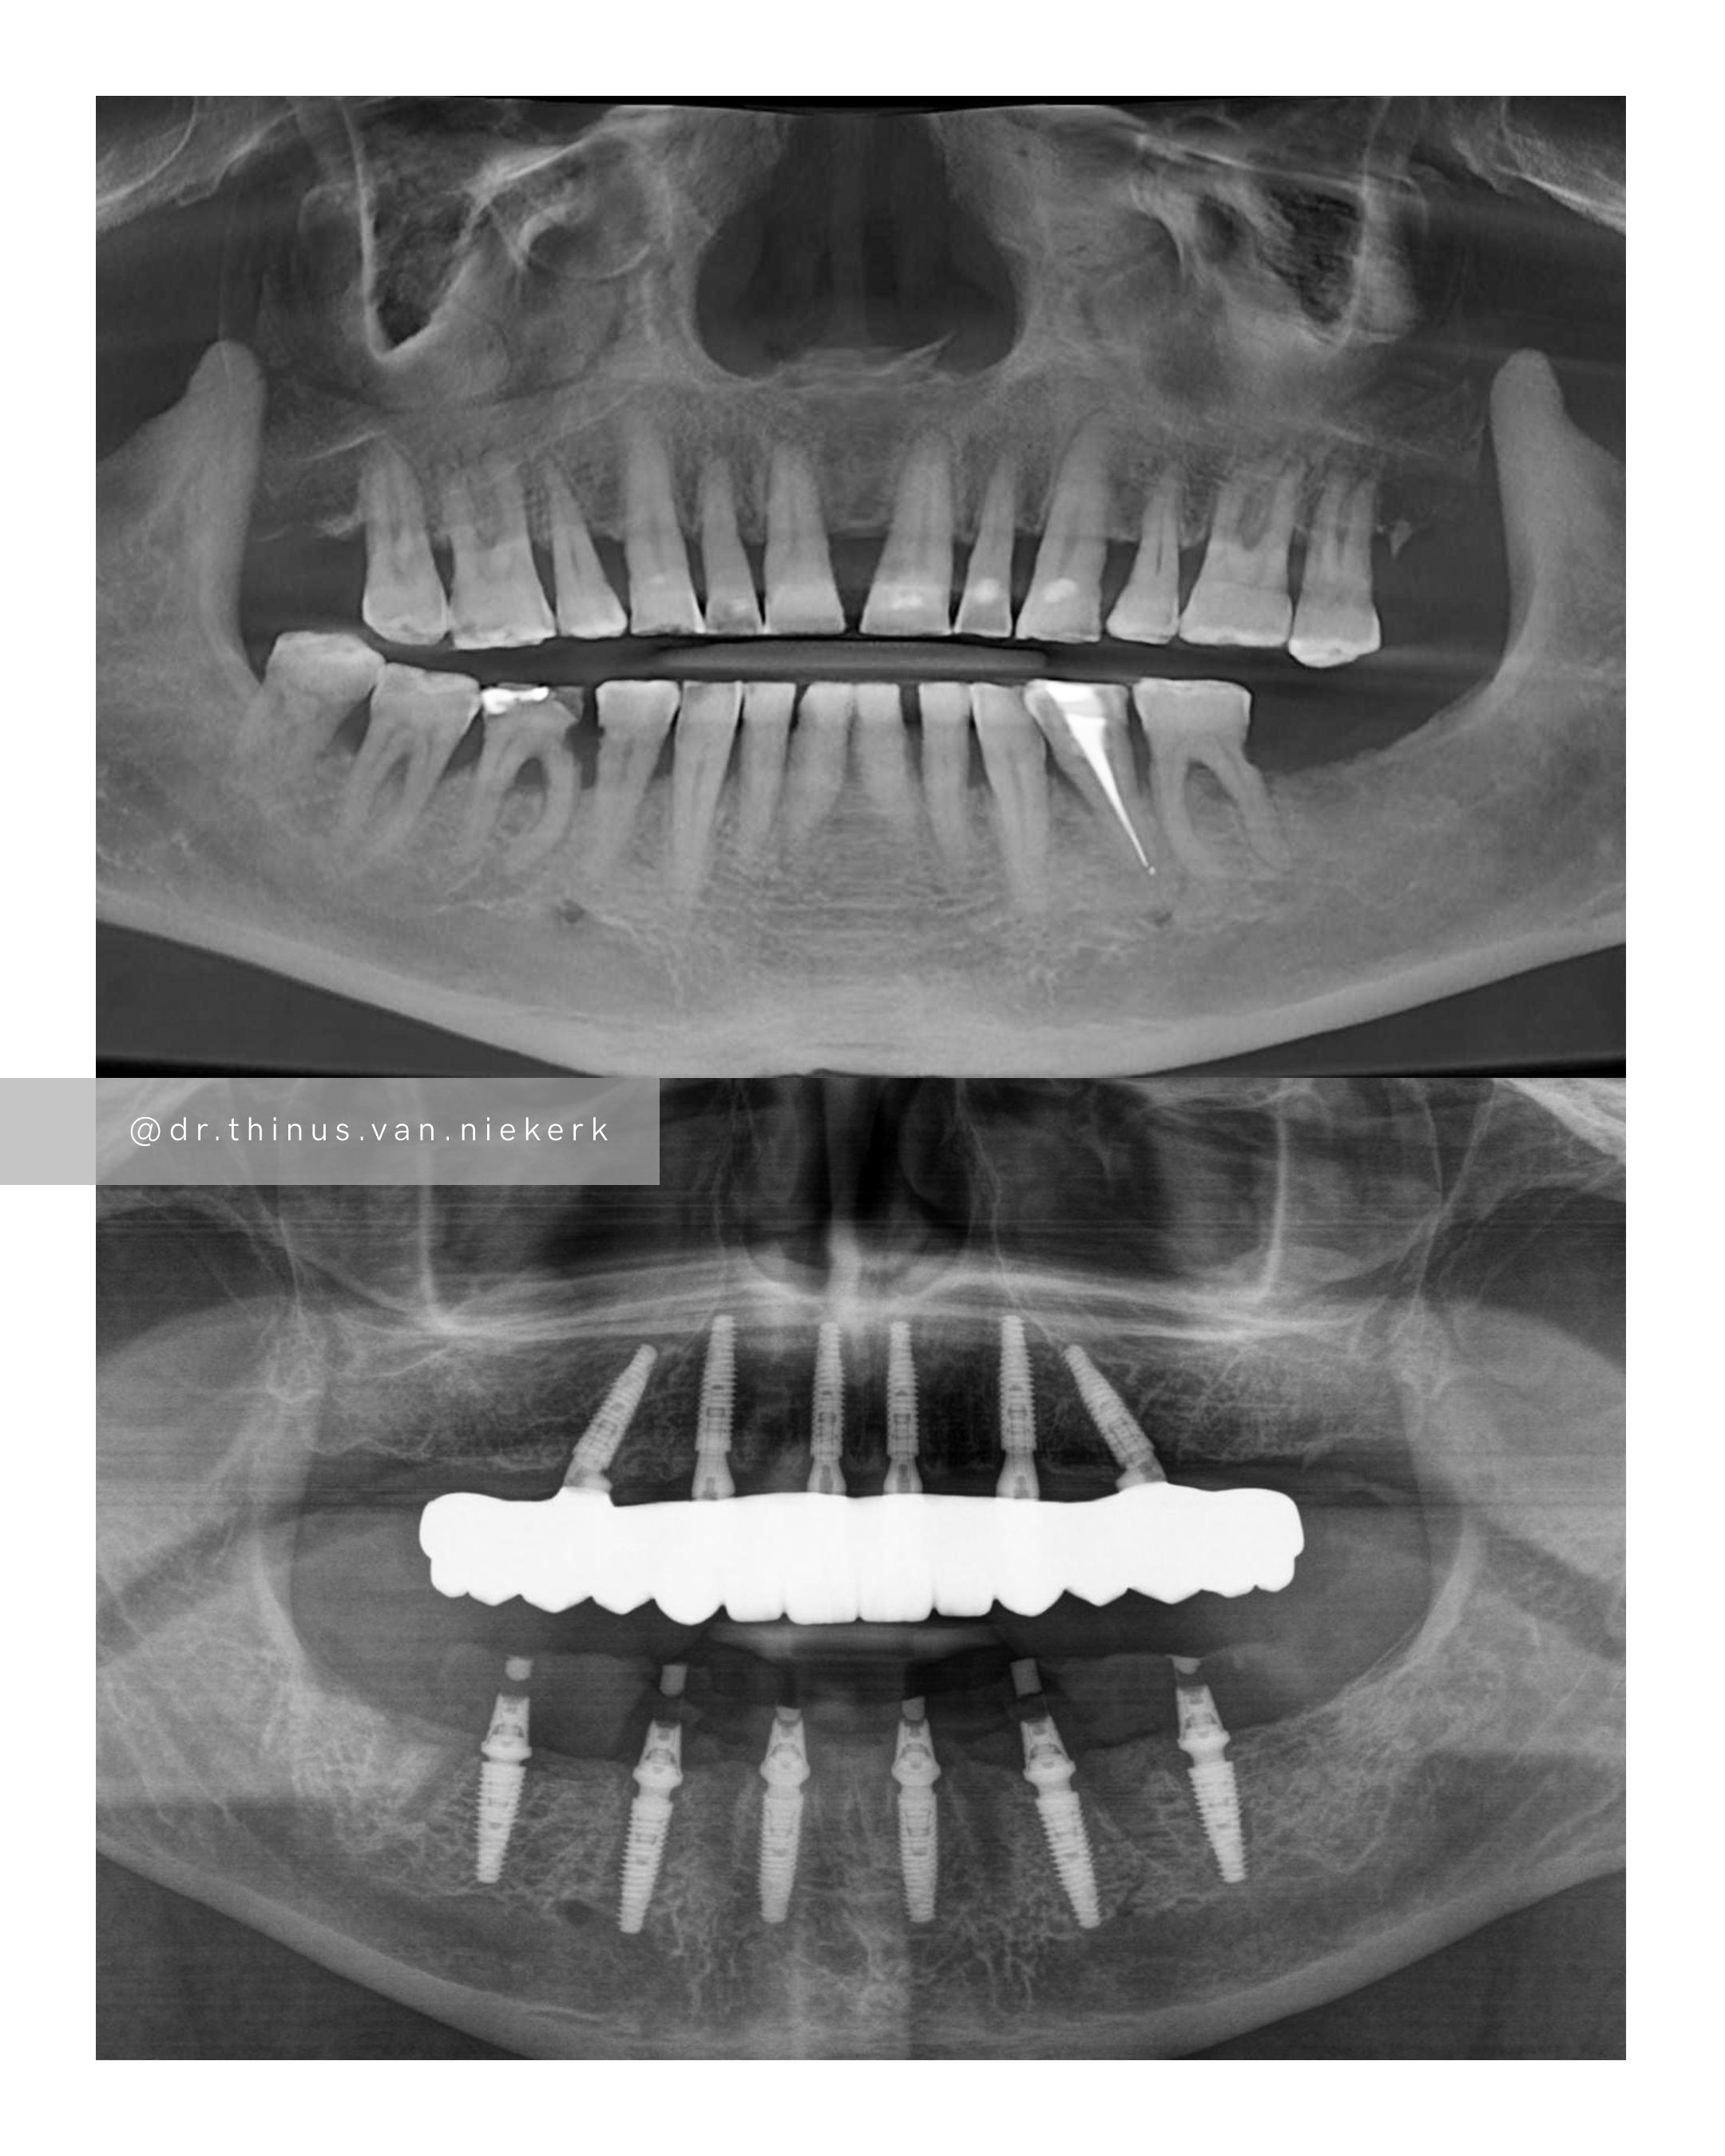

TREATMENT OBJECTIVE

Our patient endured a long history of oral disease and associated infections. Our aim was to remove all elements of infection and disease and to restore function as quickly as possible. Six fully-guided implants were placed and immediately restored with implant-supported prosthesis in both the upper and lower jaws respectively. These were then converted to final zirconia framework prosthesis as healing and tissue remodeling allowed. The complete timeline for a treatment such as this varies from 6-24 months.

COMMENTS

This was a landmark case for our clinic – being the first fully digitally-planned upper and lower rehabilitation. This case demonstrated the power and effectiveness of digital implant-surgery planning and CAD design software. No adjustments were needed at the placement of the final lower prosthesis.